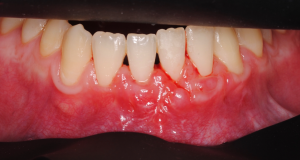

Os enseñamos este nuevo caso el Dr. Arturo Sánchez Colodro en nuestra clínica dental de Jaén, nos muestra un caso donde se puede apreciar con mucha claridad el antes y después de un caso de recesiones inferiores. Este caso ha sido tratado con la última y más avanzada tecnología en digitalización dental.

Objetivos periodontales:

- Cobertura radicular en recesión pieza 32.

- Mejora de la sensibilidad

- Estabilidad periodontal mejorando el biotipo gingival y aumento banda encía querantizada

Fotografías del proceso: